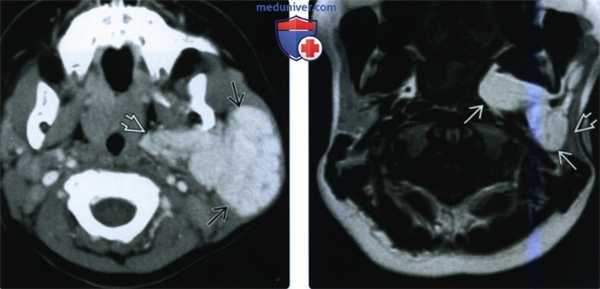

(Слева) При аксиальной КТ с КУ, выполненной девочке в возрасте одного года, определяется МГ очень большого размера, равномерно и интенсивно накапливающая контраст, практически полностью замещающая поверхностную и глубокую долю левой околоушной железы.

(Справа) При аксиальной МРТ Т1ВИ у этой же девочки восемь лет спустя определяется значительное уменьшение размеров гемангиомы и диффузное замещение ее жировой тканью. Обратите внимание на тонкую «полоску» ткани поверхностной доли околоушной железы.